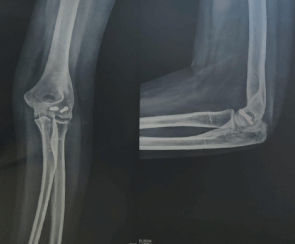

A 21-year-old female presented with pain, swelling, and limited movement in the left elbow after a fall. Radiographs revealed a comminuted intra-articular fracture involving the lateral condyle and capitellum of the humerus (Figure 1).

Figure 1: Pre-operative radiograph showing comminuted intra-articular fracture of lateral condyle and capitellum. View Figure 1